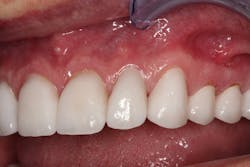

Figure 4: Provisionals

Figure 5: Provisionals

Figure 6: Provisionals

A periodontist completed the crown lengthening surgeries in three separate visits. After healing, the teeth were prepared for crowns, and provisionals (figures 4–6) were placed.